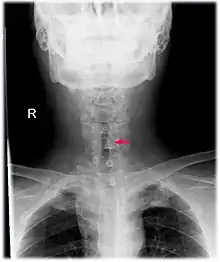

Neck AP x-ray of patient with post-intubation subglottic stenosis, as shown by the narrowing in the tracheal lumen marked by the arrow.

Subglottic stenosis is a congenital or acquired narrowing of the subglottic airway.[1] It can be congenital, acquired, iatrogenic, or very rarely, idiopathic. It is defined as the narrowing of the portion of the airway that lies between the vocal cords and the lower part of the cricoid cartilage. In a normal infant, the subglottic airway is 4.5-5.5 millimeters wide, while in a premature infant, the normal width is 3.5 millimeters. Subglottic stenosis is defined as a diameter of under 4 millimeters in an infant. Acquired cases are more common than congenital cases due to prolonged intubation being introduced in the 1960s.[2] It is most frequently caused by certain medical procedures or external trauma, although infections and systemic diseases can also cause it.

CT scans and MRI (magnetic resonance imaging) can help in diagnosis. X-rays can determine the location and size of the narrowed airway portion. Optical coherence tomography (OCT) can help observe the progression of the injury. Esophageal pH monitoring can help detect any acid reflux, which can worsen the condition. An endoscope can be inserted and used to see the vocal cords, airway, and esophagus. Spirometry is a useful way to measure respiratory function. People affected by subglottic stenosis have a FEV1 of over 10.[2]